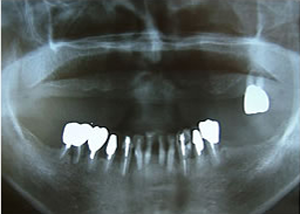

5.終了時レントゲン

治療完了

平成19年5月1日

(治療期間:2年10ヶ月)